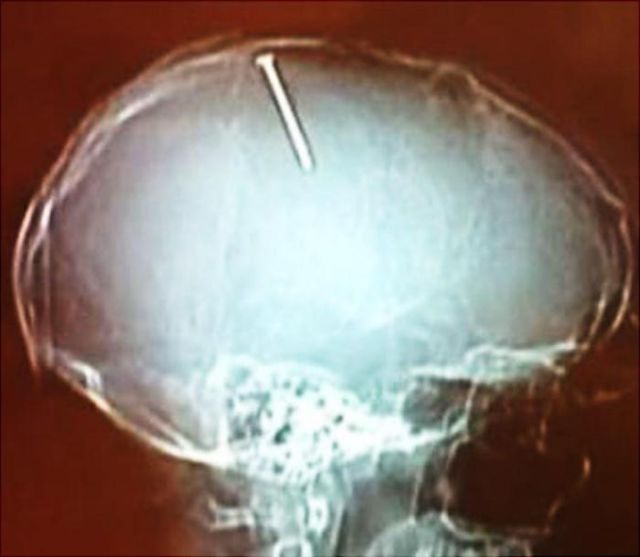

These x-rays will make you wonder how this could ever have happened in the first place.